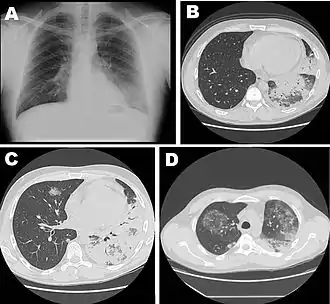

Various stages of the disease: Chest radiograph (A) and high-resolution computed tomography (B) at hospital admission, repeat high-resolution computerized tomography of the chest a week after hospital admission (C, D), shown in a 42-year-old male with severe pneumonia caused by L. pneumophila serogroup 11a

Laboratory tests may show that kidney functions, liver functions, and electrolyte levels are abnormal, which may include low sodium in the blood. Chest X-rays often show pneumonia with consolidation in the bottom portion of both lungs. Distinguishing Legionnaires' disease from other types of pneumonia by symptoms or radiologic findings alone is difficult; other tests are required for definitive diagnosis.